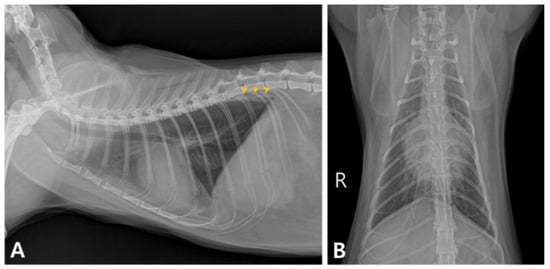

2. Case Description